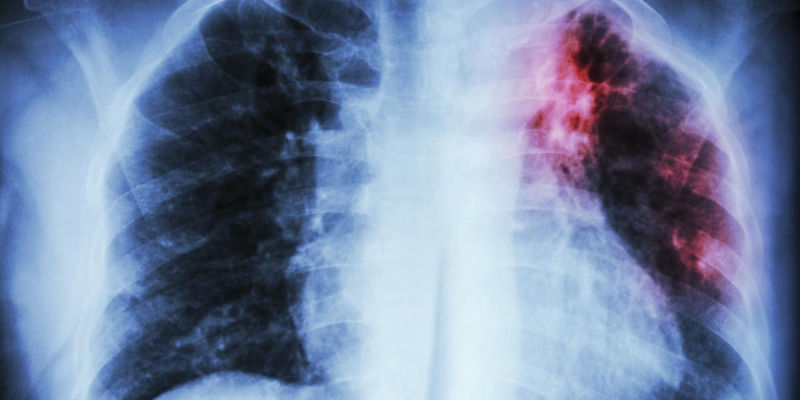

Infecções pulmonares - Pneumologista SP

Infecções Pulmonares

Pneumonias bacterianas, virais

(inclusive por COVID), fúngicas, ou tuberculose, são áreas de interesse do pneumologista. Se sintomas como tosse (com ou sem expectoração), falta de ar, febre, suor a noite, perda de peso te acompanham, uma avaliação especializada deve acontecer o quanto antes para iniciarmos seu tratamento.